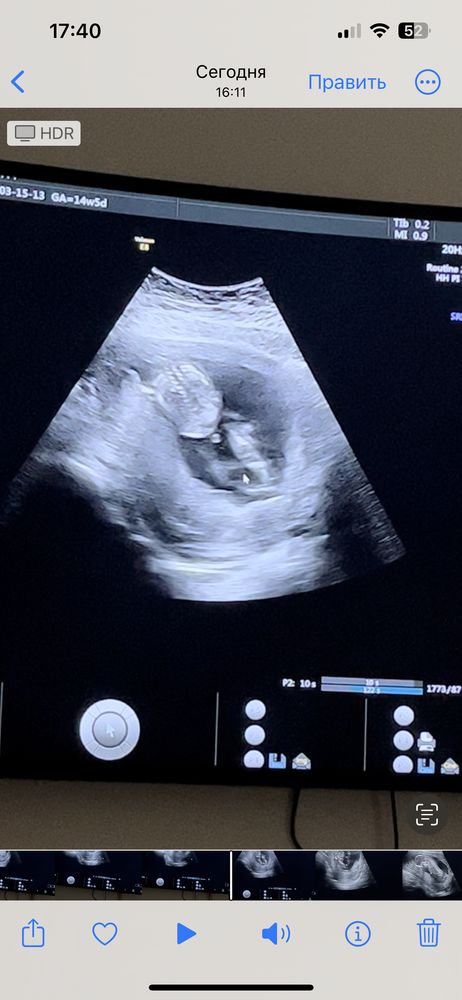

Помогите определить пол!!!

По этому фото невозможно что-то сказать)

Мальчик 100%

Диана, это яички))

С похожим узи в 16 недель подтвердили девочку

Мне кажется что наоборот девчонка

Жду девочку 🩷 1 триместр подходит к концу. Пол ребенка